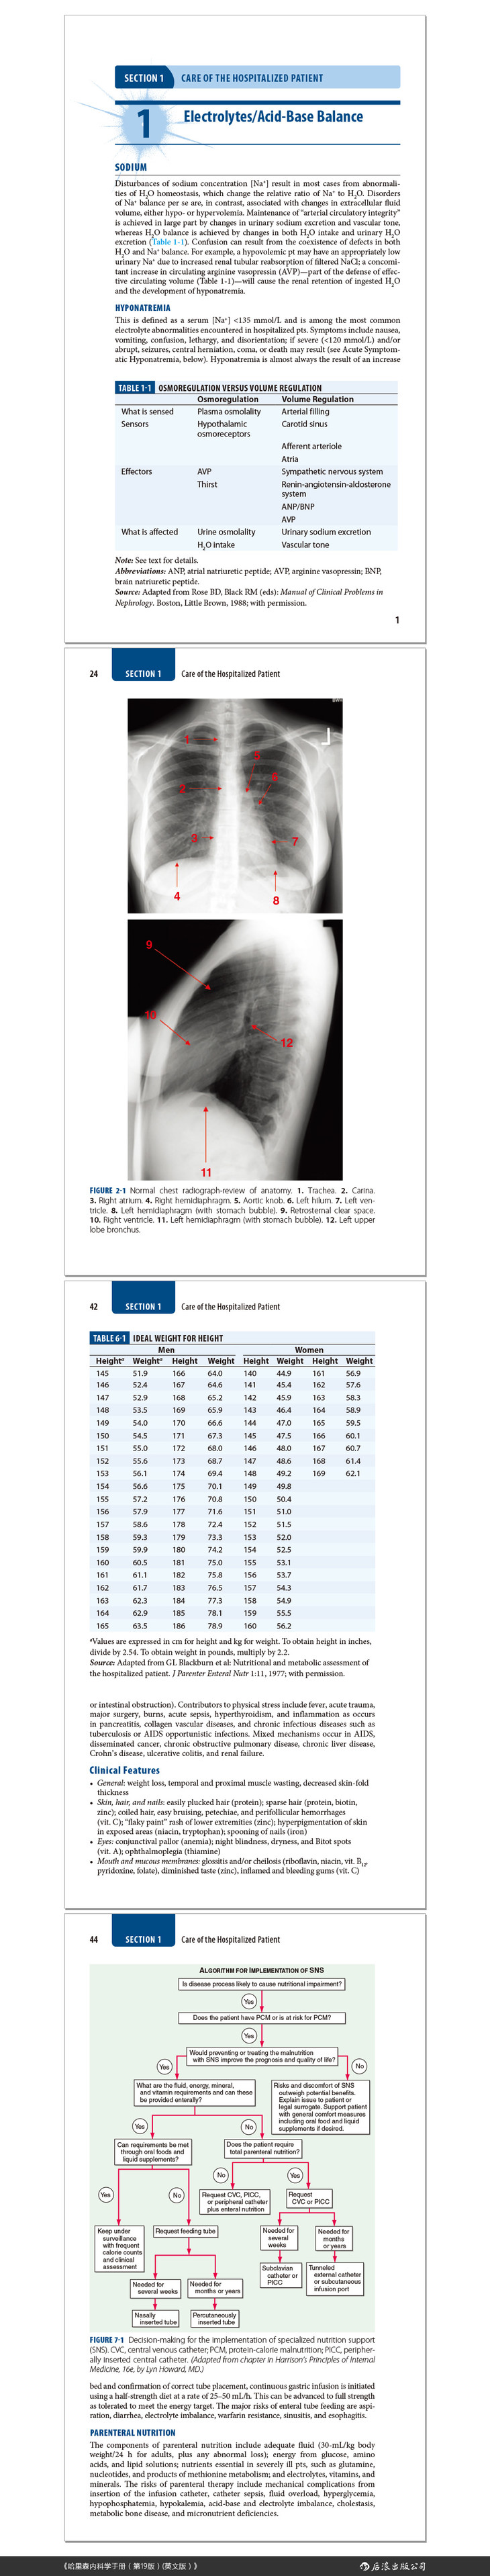

2 Diagnostic Imaging in Internal Medicine..................................23